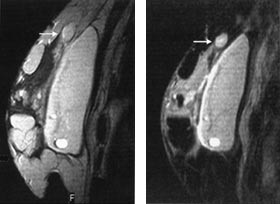

Brystkreftsvulster som er større enn 5 cm eller som vokser inn i hud eller brystvegg, behandles vanligvis med kjemoterapi eller anti-hormonbehandling før kirurgi. På grunn av problemer med å differensiere ødem og arrvev fra vitalt tumorvev er responsen på denne behandlingen vanskelig å vurdere, både klinisk og med konvensjonelle bildemetoder. Flere studier tyder på at kontrastopptak ved MR samsvarer godt med vitalt tumorvev (32, 33). Ved å registrere endringer både i kontrastopptaksmønster og tumorstørrelse er trolig MR den beste bildediagnostiske metoden for å evaluere behandlingseffekten (fig 4).